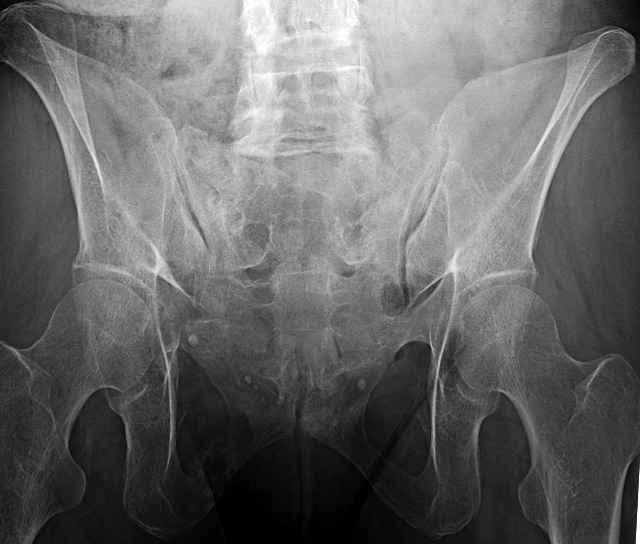

Here are a recent patient’s example slides...

54 yo Female Fell c/o Pain

Initial Films

?Instability on Exam - Limited by Pain

NonOp Initial Mgmt

3 Months After Fall

Continued Pain & Immobility

(+) Instability to Compressive Manual Exam

Pelvic CT Scan - 3 Months After Fall

Sacral Injuries

Ramus Fractures